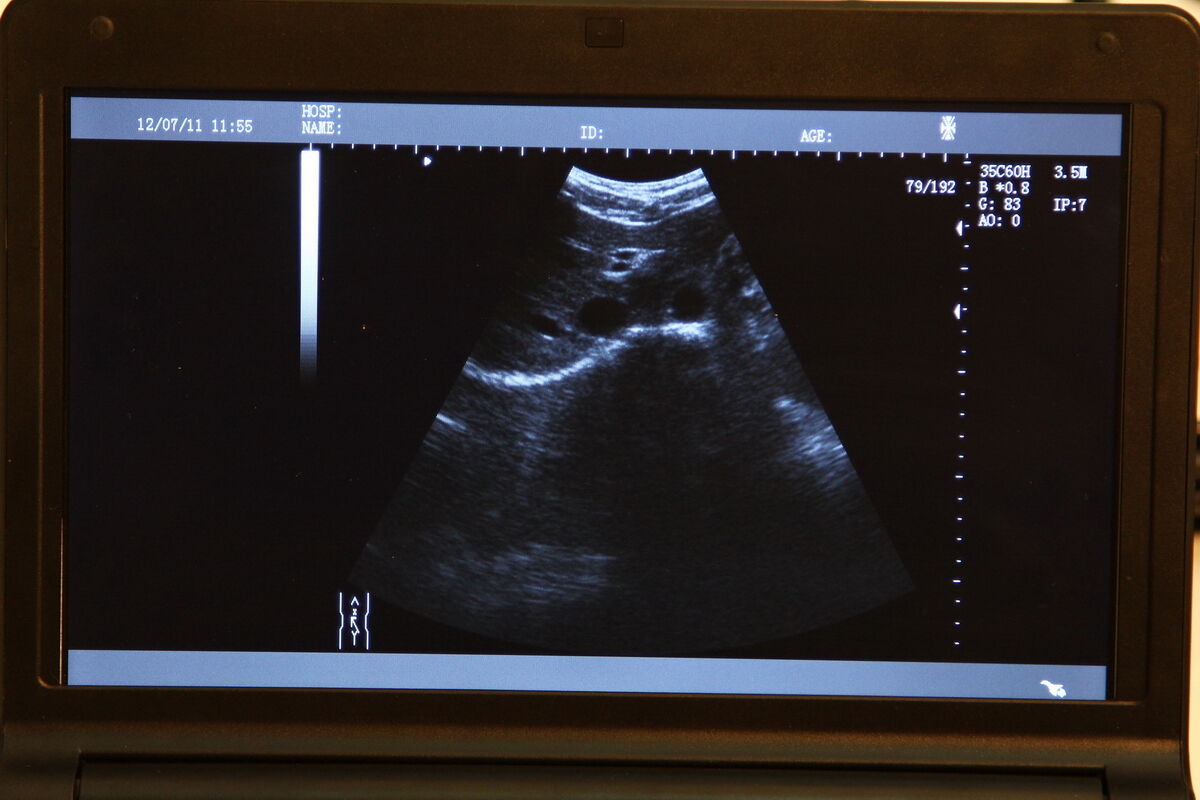

The TFT LCD Digital Laptop Linear Array Ultrasound Scanner is an indispensable tool in modern medical imaging. With advanced features that include a cavity probe machine, this portable ultrasound scanner provides high-resolution images, making it an excellent choice for healthcare professionals. But what sets it apart is its TFT LCD screen that offers clear, crisp image quality. This technology allows for better diagnostic accuracy and improved patient outcomes.

One of the standout features of the TFT LCD Digital Laptop Linear Array Ultrasound Scanner is its linear array probe. This probe is known for its high-frequency linear transducer, which is ideal for scanning small and superficial structures like tendons, arteries, and veins, so it offers precise imaging capabilities. The linear array also supports a range of applications such as musculoskeletal, emergency medicine, and vascular imaging.

Versatility is another key advantage of this ultrasound scanner. It supports a variety of probes that allow for different types of examinations. In particular, the cavity probe included with this machine is useful for gynecological and obstetric purposes. Because this adds another layer of functionality to the device, healthcare providers can deliver comprehensive care using a single machine. With multiple probe options, you can seamlessly switch from one type of imaging to another without missing a beat.